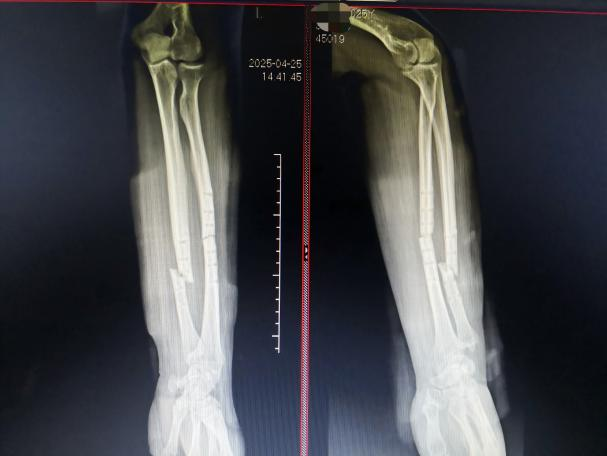

王先生1年前因左尺桡骨骨折在外院行骨折切开复位钢板螺钉内固定术。复查骨折愈合好,遂于2025.3.20返回原医院手术取出内固定。然而,术后仅1个月,在工作中搬动物品时左前臂突发剧痛,到医院检查显示左侧尺桡骨再次骨折。

经过近12周的密切诊疗和循序渐进的康复,王先生前臂肿胀疼痛迅速消退,复查X光片显示:左尺桡骨中下段呈内固定取出术后改变,断端对位对线可,骨折线由清晰逐渐模糊,肘关节、腕关节对应关系良好。